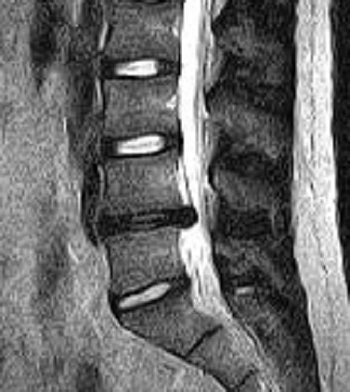

| Above, midsagittal T2-weighted MRI showed increase in stenosis at the L4 level by 2.0 mm with ventral thecal sac compression with axial loading (below). All images courtesy of Dr. Gerald Anzalone. |